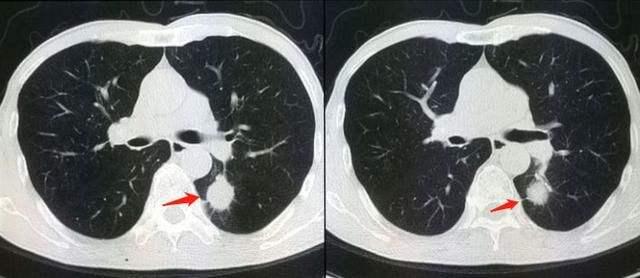

(1)双肺和气管

肺部的CT,可以检查两侧的肺部、气管和胸膜有没有异常,例如肺炎,肺部结节,肺癌,肺脓肿,肺大疱,气胸,胸腔积液,胸膜炎,肺结核,支气管扩张等等。几乎所有的肺部疾病,都可以通过肺部CT发现。其实,胸部CT还可以看有没有淋巴结转移,包括肺部的淋巴结和纵膈的淋巴结。

肺癌